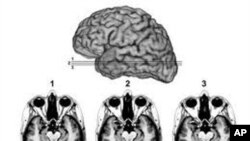

سیکھنے کا یہ عمل دماغ کے کس حصے سے منسلک ہے اس کے بارے میں اب تک کوئی بات وثوق سے نہیں کہی گئی تھی۔ تاہم حال ہی میں سائنسدانوں نے پتہ چلایا ہے کہ ڈر اور خوف کا تعلق دماغ کے ایک مخصوص حصے میں موجود ایک مخصوص اسٹرکچر amygdala سے ہے ۔ اگر اس حصے میں کوئی خرابی واقع ہو جائے یا کسی وجہ سے یہ حصہ دماغ میں موجود نہ ہو یا اسے دماغ سے نکال دیا جائے تو انسان بے خوف ہوجاتا ہے۔

سائنسدان ایک عرصے سے یہ بات جانتے تھے کہ دماغ کے اس حصے کا تعلق جذبات اور احساسات کے سیکھنے سے ہے۔ جانوروں پر کیے جانے والے تجربات سے ظاہر کرچکے ہیں کہ اس حصے کو دماغ سے نکال دینے سے ان میں ڈر اور خوف کا احساس جاتا رہاتھا۔ لیکن اس بارے میں کسی انسان پر ایسے تجربات نہیں کیےگئے تھے، اور نہ ہی سائنسدانوں کے علم میں کوئی ایسا شخص آیا تھا کہ جس کے دماغ میں یہ حصہ نہ ہو ۔ لیکن حال ہی میں سائنس دانوں کو ایک ایسی خاتون کا پتا چلا جسے کسی بھی چیز سے خوف نہیں محسوس نہیں ہوتا تھا ۔

جریدے کرنٹ بیالوجی میں شائع ہونے والی ایک ریسرچ میں ماہرین نے ایک اس عورت پر جس کا نام پوشیدہ رکھتے ہوئے اسے ایس ایم کہا گیا ہے، ڈر اور خوف کے بارے میں تجربات کیے ۔تحقیق سے معلوم ہوا کہ اس کے دماغ میں ایک مخصوص حصہ amygdale موجود نہیں تھا۔ یہ ایسا پہلا انسانی واقعہ ہے،جس کا انکشاف آئیوا یونیورسٹی کے سائنسدانوں نے جریدے کرنٹ بائیولوجی میں کیا ۔